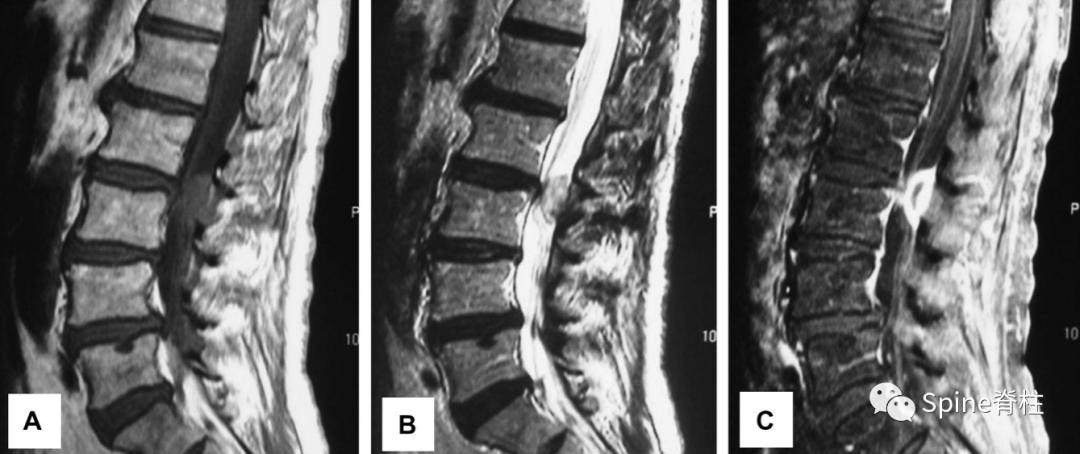

发表在顶级四大医学期刊之一的NEJM的最经典病例:患者为29岁女性患者,因“右小腿疼痛、感觉异常”就诊,大小便正常。起始腰椎磁共振提示腰4-5椎间盘突出并椎管狭窄,神经根压迫严重(左图)。她选择保守治疗,5个月后,复查腰椎磁共振惊奇的发现突出的椎间盘被吸收了,且临床症状完全缓解。

但既往文献报道腰椎间盘突出自发性重吸收的文献,多为病例报道,从证据等级角度来说,是低级别证据,相对参考可信度低(举个不恰当的例子,就好比天气预报明天会不会下雨?中央电视台预报的可信度相对高些,但县级天气预防的可信度就低些了,而文献中报道的腰椎间盘突出自发性重吸收的文章证据等级属于县级天气预报水平)。

另外,从另一个角度来说,腰椎间盘突出重吸收发生率是很低的,也就是大部分腰突是不会发生重吸收的。 因此,我们不能把所有赌注都压在小概率的“重吸收”上。